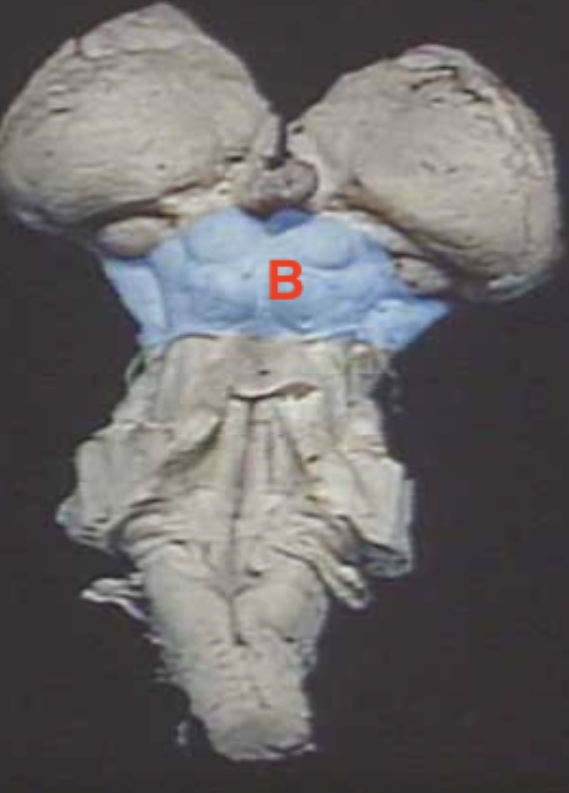

A

Hypothalamus + Thalamus

B

Midbrain

C

Pons

D

Medulla oblongata